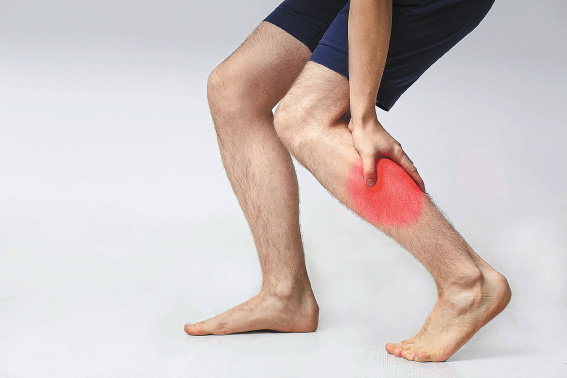

운동을 하거나 평상시 생활을 하다 보면 특정 부위 근육 통증이 느껴지는 것을 볼 수 있습니다. 더 심해진다면 방치하지 말고 진료 및 치료를 받는 것이 좋습니다. 오늘은 그 부위 중에서 흔하게 발생하는 종아리 근육 통증 원인에 대해서 알아보도록 하겠습니다.

우선 종아리 근육 통증이 느껴진다면 가장 먼저 의심해 볼 필요가 있는 것이 바로 종아리 혈액순환 장애입니다. 종아리는 신체 부위 특성상 제일 하단에 위치하고 있어서 혈액순환이 잘 되지 않을 수 있습니다.

혈액순환이 잘 되지 않기 때문에 많이 걷거나 운동을 할 경우에 종아리가 붓거나 통증이 느껴질 수 있습니다. 또한 평소 종아리 근육을 사용하지 않는다면 갑자기 근육통이 올 수 있기 때문에 평소 생활습관이 중요합니다.

종아리 근육 통증 원인 다른 이유는 종아리 근육 파열을 의심해 볼 수 있습니다. 만약 종아리에 무리한 충격을 가하거나 근육이 노화로 인해서 자그마한 충격에도 쉽게 파열될 수 있으니 각별히 주의하시기 바랍니다.